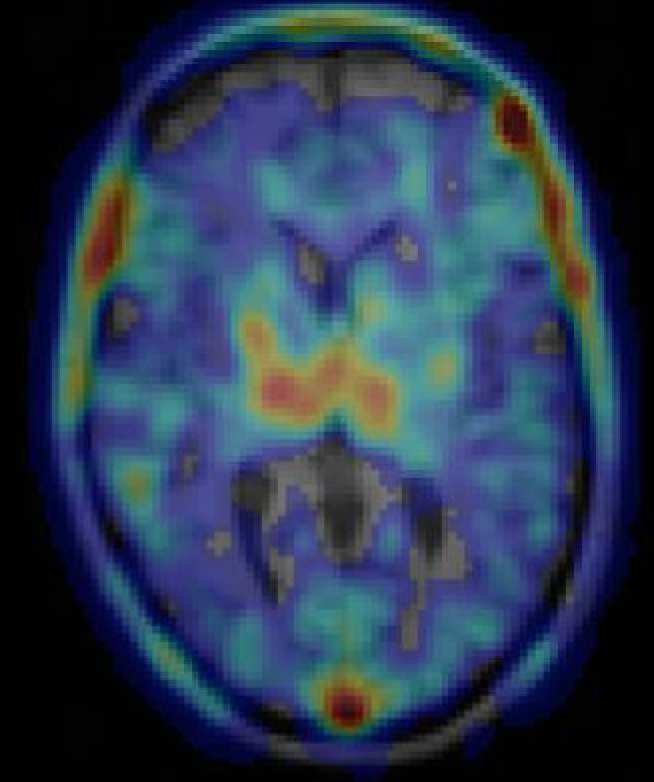

Traumatic brain injury (TBI) is the most common cause of death and disability in young adults. Approximately 25% of TBI patients improve but an equal number deteriorate over time. We know little about why patients vary so much in how they recover. Recently, using a Positron Emission Tomography (PET) scan, abnormal persistent brain inflammation (chronic neuroinflammation) has been detected following TBI. Treating chronic neuroinflammation may improve brain recovery. The antibiotic minocycline has been shown to have anti-inflammatory effects and to protect the brain in animal studies of TBI. In this study, we investigate whether minocycline therapy reduces chronic neuroinflammation following TBI, measured using PET. PET scans allow us to measure inflammation directly. We use Magnetic Resonance Imaging (MRI), performed at the Clinical Imaging Facility (CIF), to measure brain structure and function after TBI, and to look for evidence of inflammation using magnetic resonance spectroscopy (MRS).